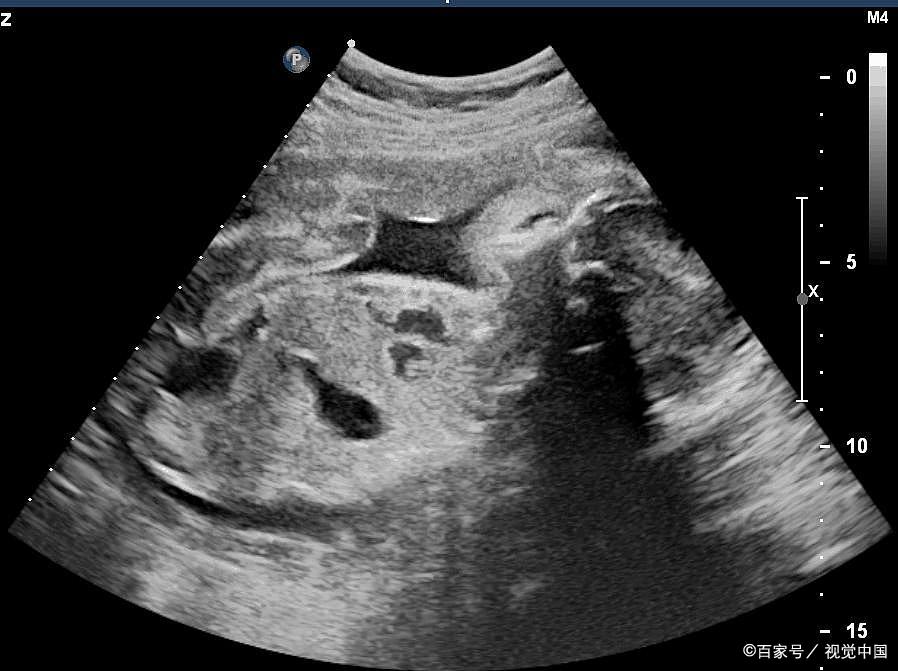

P11 子宫内的胎儿、脐带和胎盘关系的示意图知识补充

1.胎儿生活在母体内,胎儿生长发育过程中所需要的各种营养物质,都是通过胎盘从母体中获得的。如果孕妇喝酒、吸烟(包括被动吸烟)或者吃了某些药品,酒精、*草烟**和这些药品中的有害物质,就会通过胎盘和脐带到达胎儿的体内,对胎儿的生长发育产生不良影响。